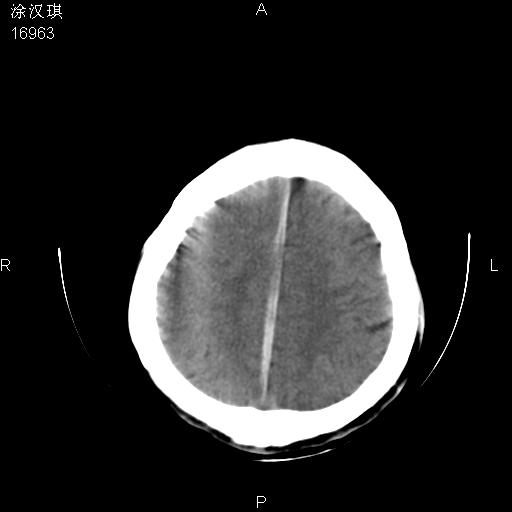

以下是引用chinazhouhua在2008-5-1 12:06:00的发言:[br]影像上来看,这是个典型的硬膜下血肿,包括右侧额颞部、大脑镰下、小脑幕下,而且在右侧额颞顶枕部、大脑镰下没看到高密度出血向脑沟内延伸,但是小脑幕下硬膜下有时候和蛛血不是很好鉴别,而且硬膜下很多时候伴有蛛血,往往在复查的时候出来,所以这种病人还是应该考虑硬膜下血肿伴有蛛血。

以下是引用zsl6918在2008-5-1 15:34:00的发言:[br]本病例主要表现为急性硬膜下血肿。